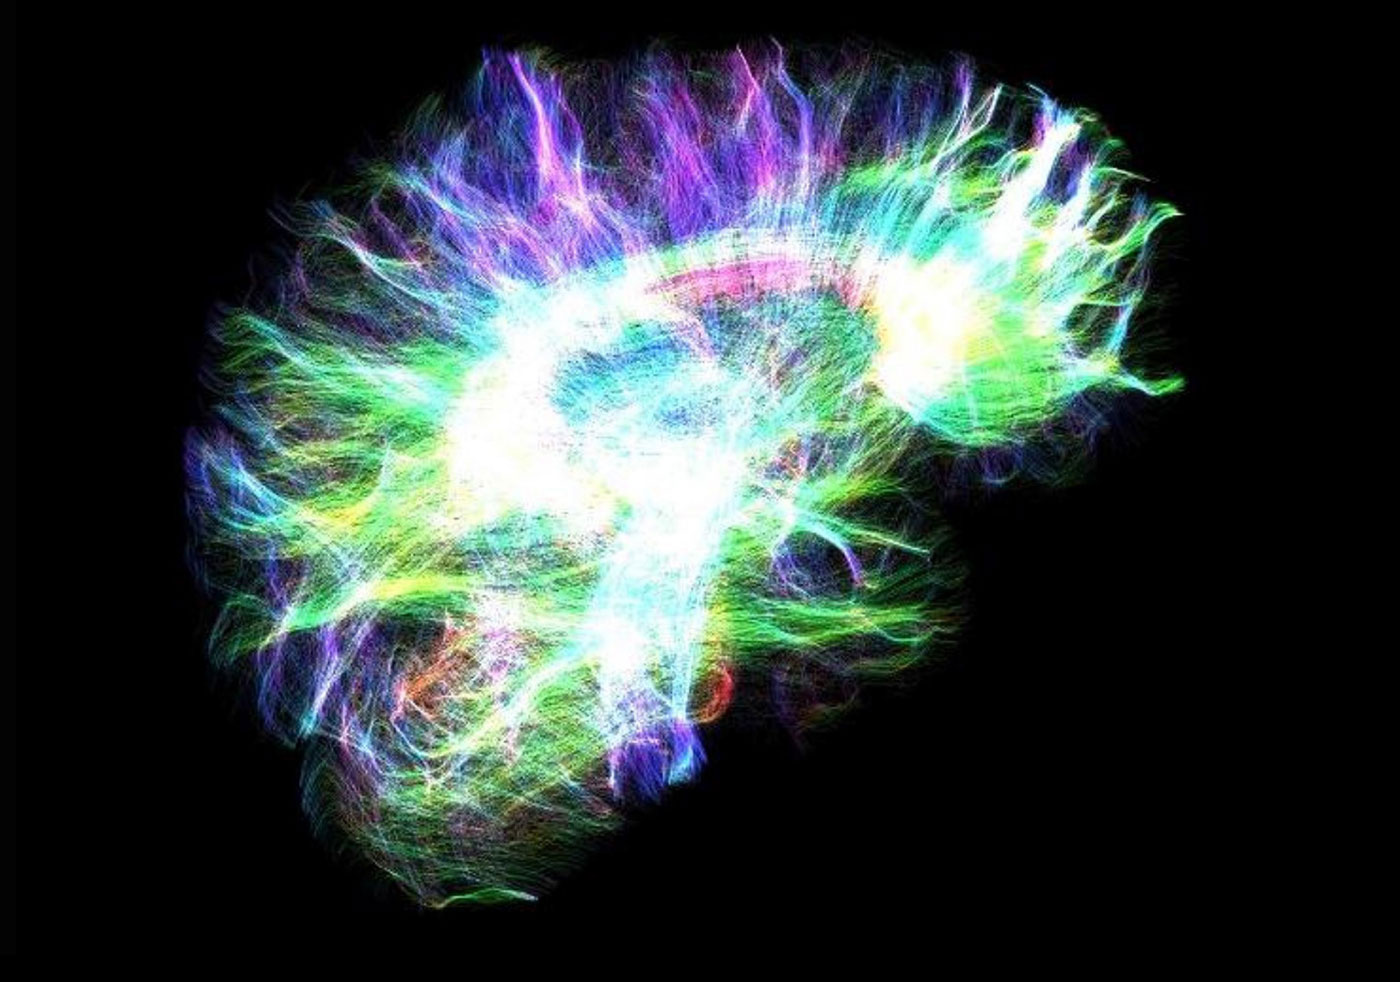

High angular diffusion imaging

The neuroscience team used 257 different directions, 23 b-values and a maximum b-value of 4000 s/mm² to collect the data below in a total scan time of 11 minutes. The higher number of gradient directions combined with multiple b-values not only allows for improved fiber tracking in these examples, but also enhances the analysis of intra-voxel incoherent motion (IVIM) and diffusion kurtosis (DK) effects in one single measurement.

High angular diffusion imaging

The neuroscience team used 257 different directions, 23 b-values and a maximum b-value of 4000 s/mm² to collect the data below in a total scan time of 11 minutes. The higher number of gradient directions combined with multiple b-values not only allows for improved fiber tracking in these examples, but also enhances the analysis of intra-voxel incoherent motion (IVIM) and diffusion kurtosis (DK) effects in one single measurement.